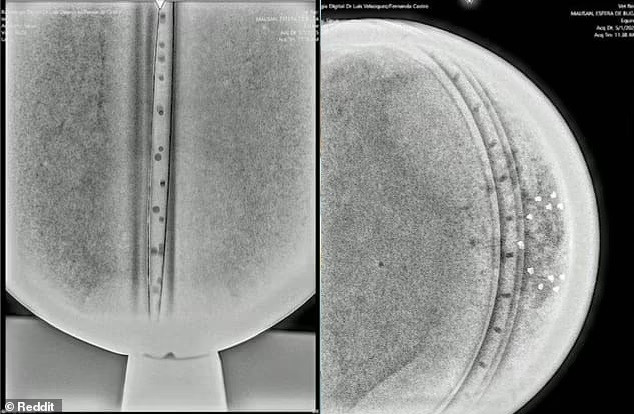

Phân tích X-quang cho thấy cấu trúc bên trong tinh vi, gồm 3 lớp kim loại, một “chip” trung tâm và 18 điểm nhỏ sắp xếp có chủ đích – điều không phổ biến trong công nghệ nhân loại.(Ảnh: Daily Mail)

Không có dấu hiệu hàn nối, vật liệu có độ đặc giống xương người, càng làm dấy lên nghi vấn về nguồn gốc ngoài hành tinh.(Ảnh: Daily Mail)